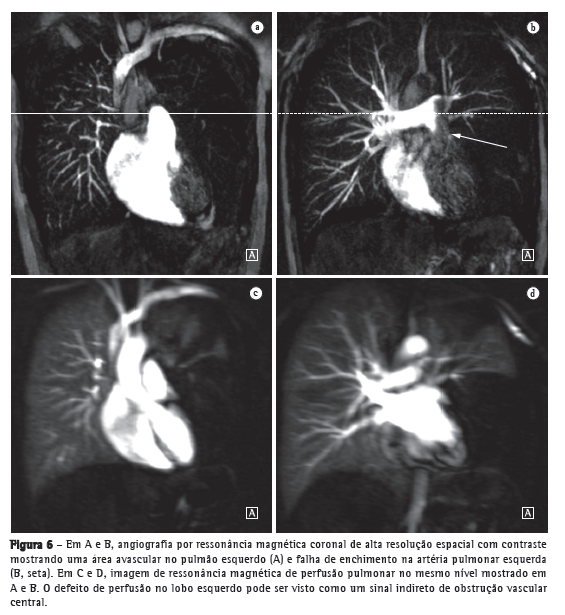

Avanços técnicos substanciais em angio-RM pulmonar foram introduzidos nos últimos anos (Figuras 5 e 6). Novas melhorias estão em andamento; dentre elas, o uso de imagens paralelas, compartilhamento de visão, angiografia do tipo time-resolved echo-shared(17-19) e perfusão pulmonar. Essas técnicas encurtaram o tempo de aquisição da angio-RM, tornaram-na menos suscetível a artefatos de movimento e melhoraram a resolução espacial. Um estudo mostrou que um protocolo combinado de RM (progressão de RM em tempo real para RM de perfusão, e desta para angio-RM) é confiável e sensível, produzindo resultados semelhantes aos obtidos com TC com multidetectores de 16 fileiras.(18)

Hipertensão pulmonar

O uso da RM permite uma avaliação abrangente da hipertensão pulmonar, sendo que a angio-RM e sequências de perfusão permitem a identificação e diferenciação de embolia pulmonar e outras entidades.(22,23) Além disso, a angio-RM permite uma avaliação detalhada da localização do material tromboembólico e, para o planejamento cirúrgico, a angio-RM é tão útil quanto a angiografia por subtração digital e a angiografia por TC.(24,25) Na RM, as sequências de perfusão podem ser avaliadas quantitativamente, o que permite que a gravidade da doença de pequenos vasos seja avaliada. A redução da perfusão correlaciona-se com a gravidade da doença, e resultados preliminares sugerem que a perfusão é um substituto sensível para o monitoramento da doença.(4) Imagens estruturais do pulmão permitirão a exclusão de doenças do parênquima pulmonar. Medidas de fluxo sanguíneo e pressão cardíaca direita permitem que se estimem a pressão arterial pulmonar e o esforço cardíaco e facilitam a identificação de doença valvular concomitante.